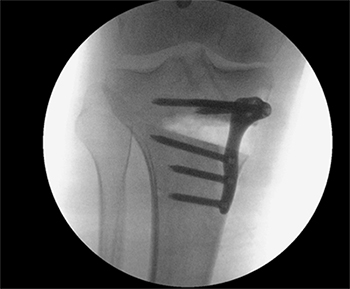

In the knee realignment procedure, the bone is cut 80% of the way across and then bent by a predetermined amount and fixed in place with a metal plate and screws. Sometimes bone is used to fill in the gap created by cutting and bending the bone.

In patients who are bow legged the tibia is normally cut just below the knee (High Tibial Osteotomy).